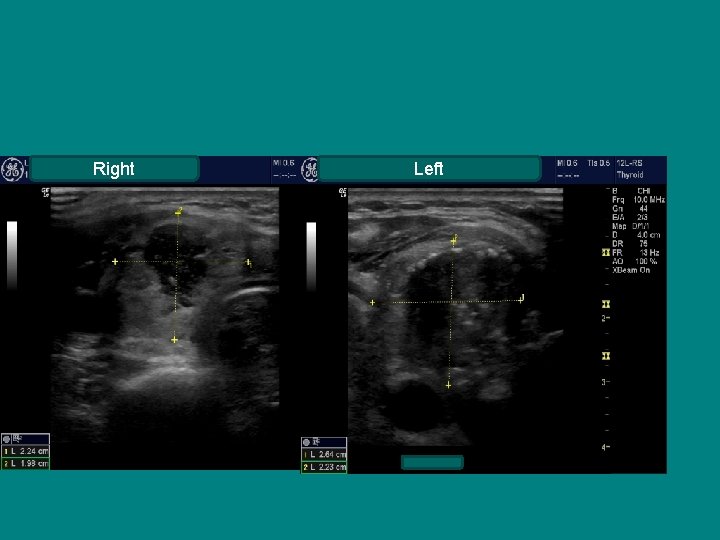

Right Left

TOXIC MNG

Normal TSH with Irregular gland